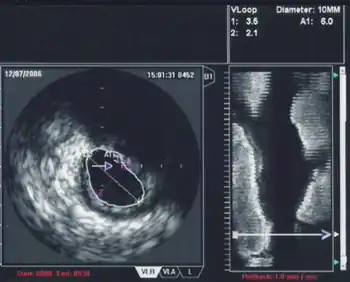

3D Echocardiography

3D TEE is a technology developed to improve upon the limitations of 2D tomography. With the introduction of the matrix TEE probe, 3D TEE can collect real-time 3D images that provide a comprehensive view of the heart structures, leading to better understanding and decision making during cardiac procedures. The technique acquires a volumetric data set and displays it in custom orientations, allowing for greater depth and understanding of heart structures compared to 2D echocardiography.[7]

Intravascular ultrasound, also known as a percutaneous echocardiogram is an imaging methodology using specially designed, long, thin, complex manufactured catheters attached to computerized ultrasound equipment to visualize the lumen and the interior wall of blood vessels.